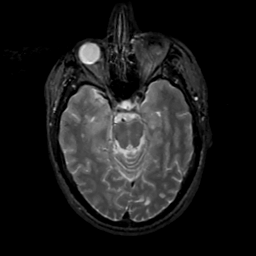

MR Study #12, May 12, 1991 -- Slice #18